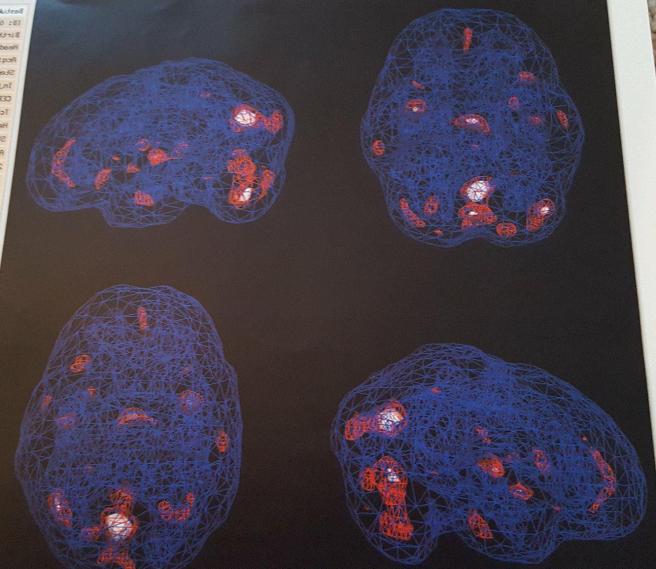

brain 2.jpg

This is my brain without any stress or concentration. The white and red indicate activity.  So, here my brain is functioning pretty well.

brain 1

This scan shows the activity in my brain when under stress or having to really concentrate.  Much of the activity decreased in most areas of my brain.

Basically what these two particular scans are showing is that when I have to think really hard or am put into stressful situations, my head short circuits.  At other times, I get hyper-focused and obsessive about certain thought patterns.  Most of the time I’m able to compensate for this fairly well, and now that I understand what is going on, I can plan ahead for some of my brain farts. But sometimes, especially if I’m put on the spot with a question or task when I’m already nervous, I am left paralyzed and clueless.